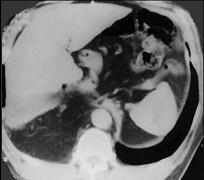

问题 女,43岁,急性胸骨后剧痛,腹痛腹胀、呕吐,影像检查如图,最佳的诊断是 ( )

选项 A.后纵隔神经源性肿瘤 B.右下肺癌 C.食管裂孔疝并胃扭转 D.后纵隔畸胎瘤 E.后纵隔脓肿

答案 C